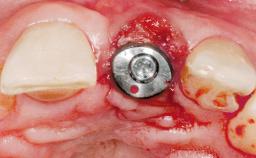

A 30-year-old female patient had lost tooth 21 and was referred to our clinic for consultation and treatment. Due to advanced apical infection, tooth 21 had been extracted two months earlier at another clinic and an acrylic-resin tooth had been bonded to the adjacent teeth. The patient desired implant treatment to avoid any damage to the adjacent natural teeth. While the patient had no history of any systemic disorder, she was a heavy smoker and exhibited medium to advanced periodontitis in the entire jaw. After the initial treatment to achieve a pocket probing depth of less than 4 mm and no bleeding on probing, a decrease in the height of the papillae mesial and distal to the extraction site and overall gingival recession were observed.

Bone Augmentation Horizontal|Staged

Augmentation Materials Autogenous chips|Membrane

Soft Tissue Grafting Simultaneous